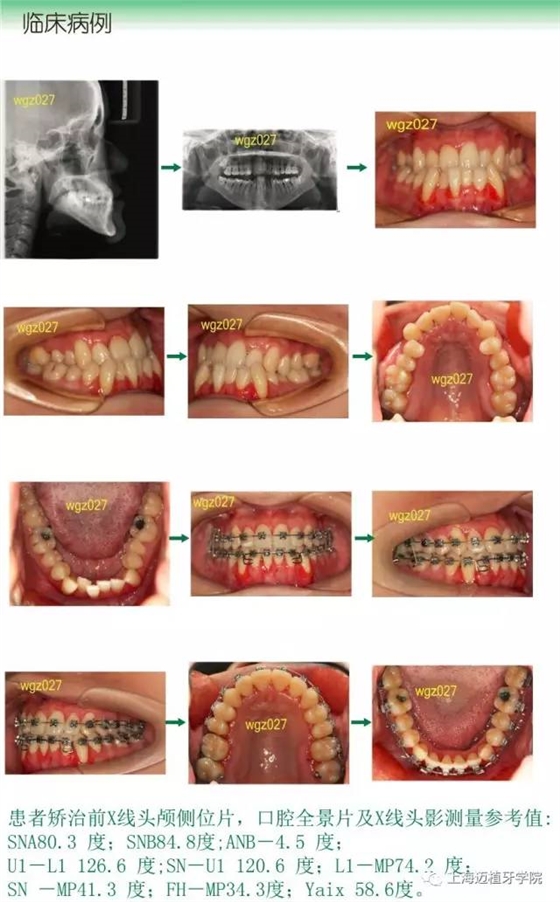

3、安氏III類錯(cuò)合畸形的病例診斷分析及矯治流程

9、骨性錯(cuò)合的正畸掩飾性治療